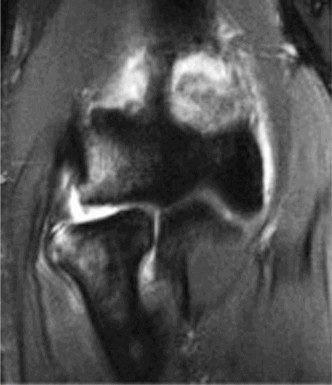

A patient is known to have a SLAP tear. An MRI shows a large cyst in the spinoglenoid notch. What additional finding on examination is the patient likely to display?

Explanation:

Weakness in external rotation. Compression at the spinoglenoid notch will affect only the infraspinatus as the suprascapular nerve has already innervated the supraspinatus by this point. Compression at the suprascapular notch will affect both the supraspinatus and the infraspinatus. Prolonged impingement on the suprascapular nerve by a spinoglenoid cyst can result in atrophy of the infraspinatus muscles. This would show up as weakness in external rotation on examination. These cysts are associated with SLAP lesions and are formed 40 by a one-way valve effect, where synovial fluid can exit the joint into the cyst but not drain spontaneously.